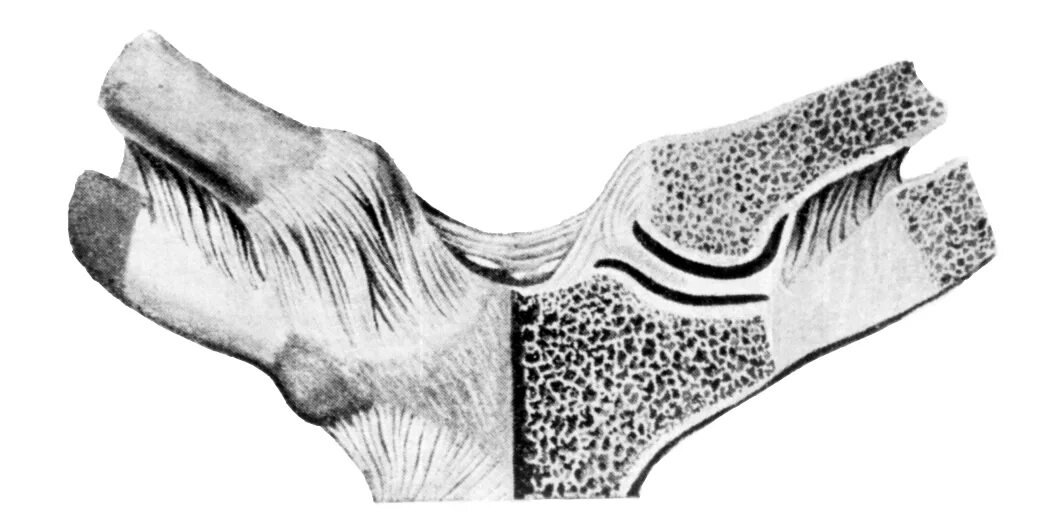

Грудино ключичная артрит